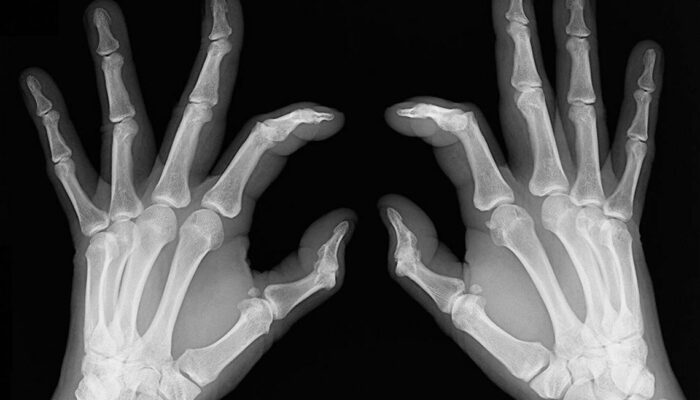

- Bone deformation: Arthritis also attacks the bones and makes them crooked and stiff. Look out for signs of any subtle changes in your joints and test them for pain levels.

Rheumatoid arthritis causes chronic inflammation of joints, which results in joint pains, inflammation and bone deformation. It usually starts slowly with pain in some parts of the body that can come and go in the beginning and then spread within weeks or months. It is better in this day and age to always be aware of your health problems and not to ignore slightest of joint pains.